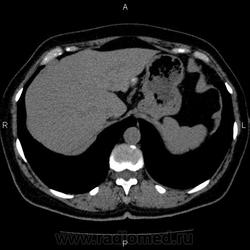

- https://radiomed.ru/sites/default/files/styles/case_slider_image/public/user/5278/10002_0.jpg?itok=S-d8_IwS

Это кальцификация. Бывшая гематома, бывший воспалительный процесс, паразитарное поражение, гемангиома, сосудистая мальформация, злокачественное нечто либо метастаз. Без клиники, пола, возраста и болюсного КТ... ну допустим, я поставлю на солитарный метастаз. И это 50/50, т.е. либо я права, либо нет.

гидативную нежизнеспособную кисту. Гемангиома гиподенсна относительно здоровой паренхимы, да и гематома так выглядеть не может.

На эхинококковую кисту похожа

Похоже на кальцинированную эхинококковую кисту печени; для уточнения КТ с болюсным мультифазным контрастированием; консультации гастроэнтеролога и онколога.

"Образование" 3 года без динамики. На УЗИ написали гемангиому. Спасибо всем.